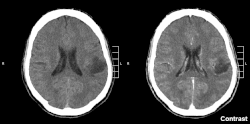

| Glioma in the left parietal lobe (brain CT scan), WHO grade 2 | |